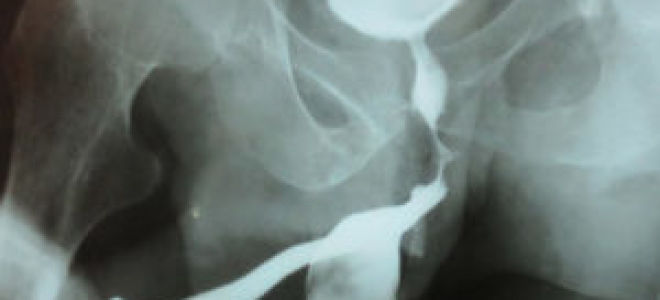

Ретроградная и микционная уретрография у мужчин: что это

Уретрография у мужчин позволяет выявить большое число заболеваний мочеполовой системы.